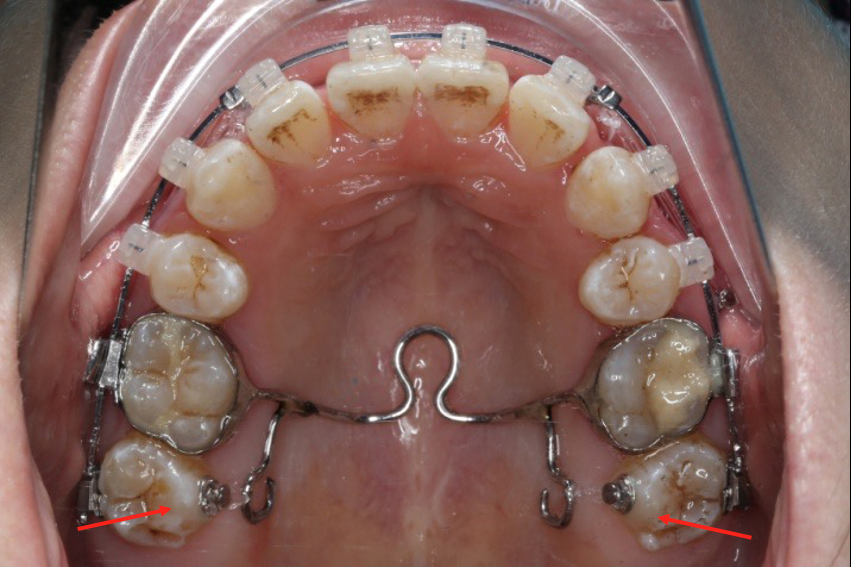

上后牙:高度保持不变/压入性移动,尽量避免伸长;▲垂直向控制中,应防止上后牙颊侧倾斜(TPA);▲腭尖高度控制也重要。

下后牙: 向前,整体移动利于咬合支点前移(Power arm);▲向前,倾斜移动易导致咬合平面后下旋转;▲后牙压低/全牙弓压低利于咬合平面逆时针旋转。

长时间使用TPA或者使用颌内支抗关间隙,容易造成第一磨牙和第二磨牙颚侧尖出现台阶,容易造成术后早接触及咬合关系不良

(引用其他病例图片)